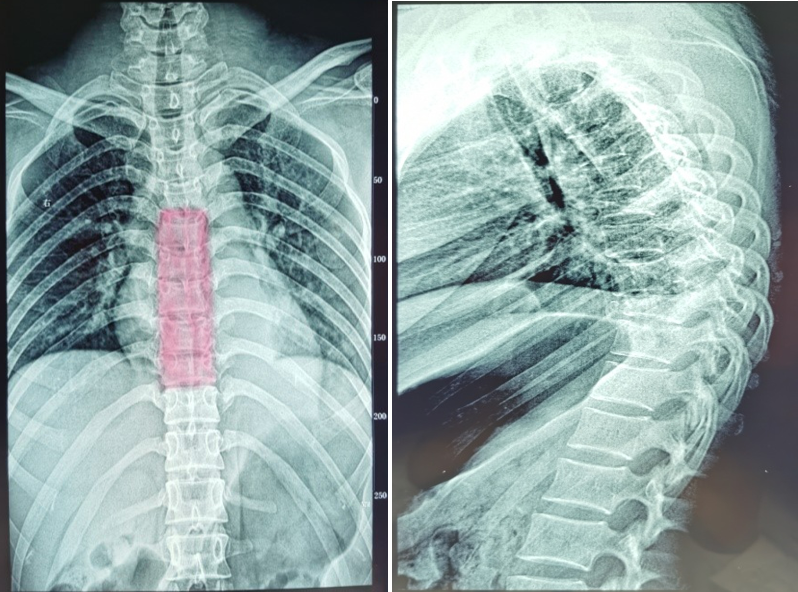

黎燕清,女,56岁,胸椎后凸畸形,t8,9椎体骨折,as并al,op,清远职工医保

胸椎正侧位x线:提示胸8,9骨折脱位,胸5,6,7椎体骨折.